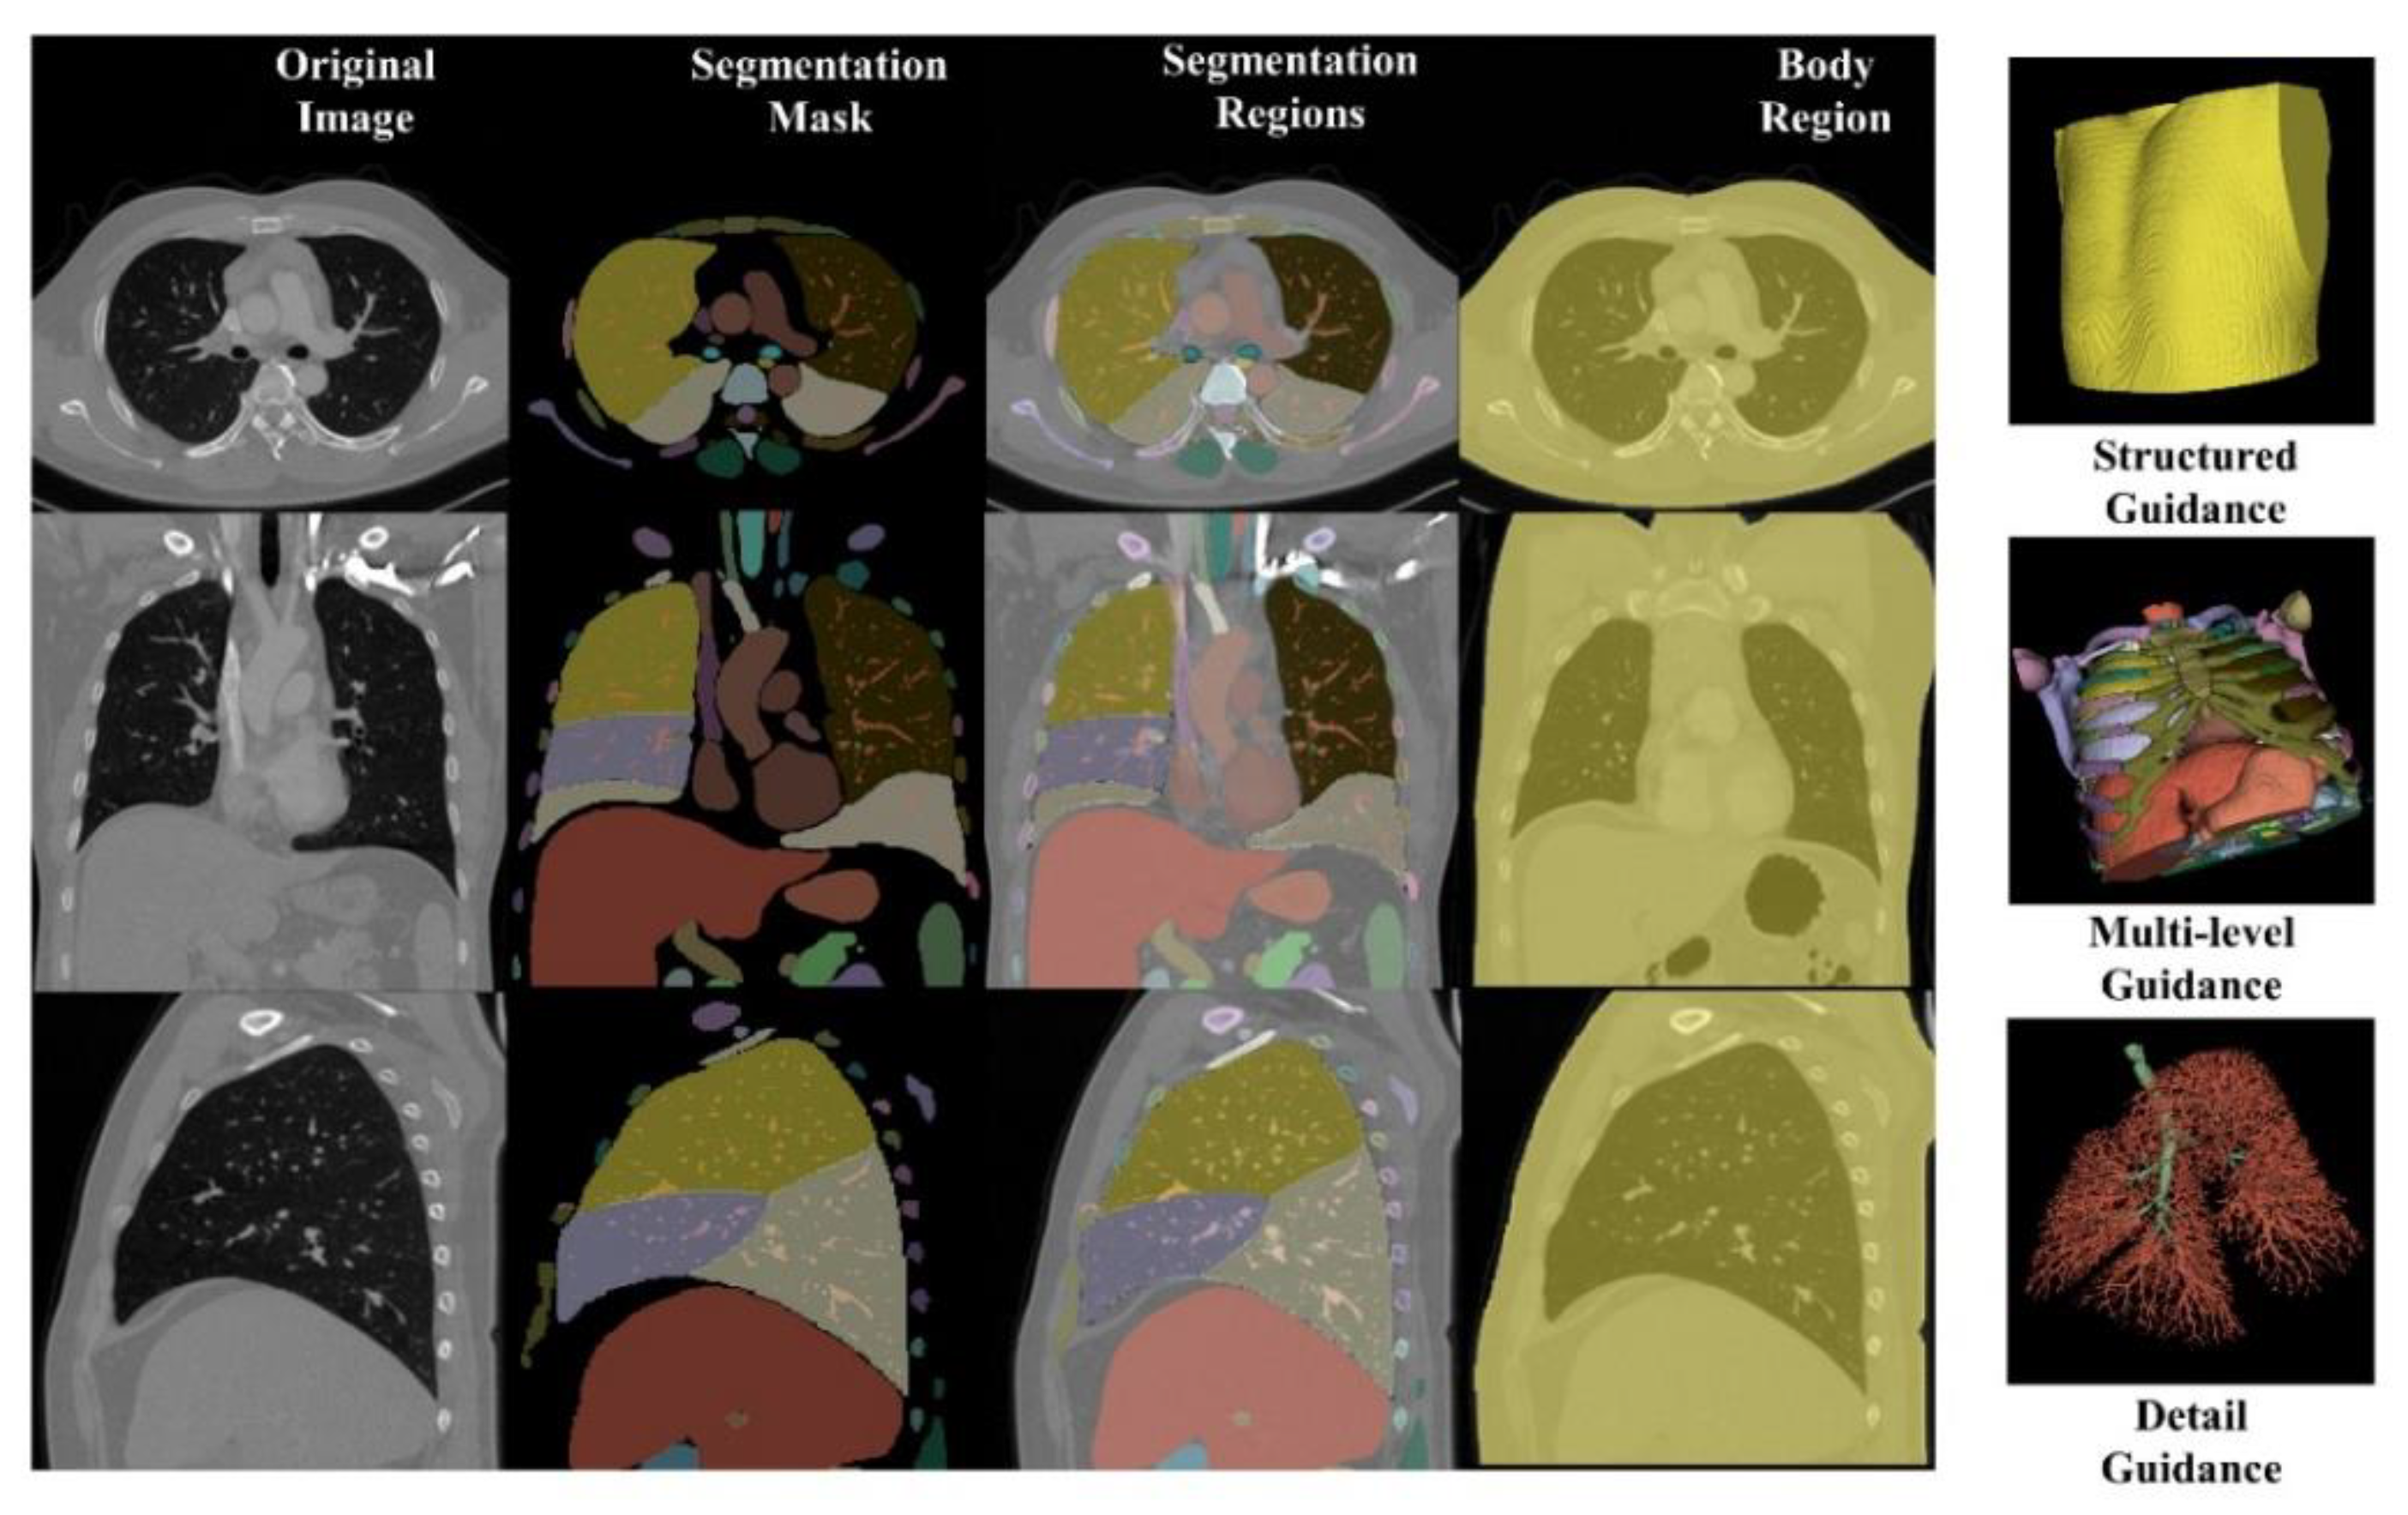

| Algorithm 1 Artifact reduction using diffusion with segmentation guidance |

| Input:input image ,concatenated guidance made by model Seg,noise level N |

| Output:output domain image |

| for all t from N to 1 do |

| end for |

| return |